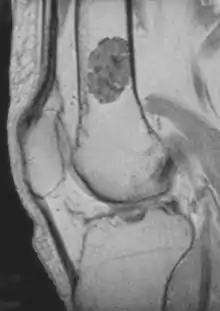

- magnetic resonance imaging (MRI)[1] - a diagnostic procedure that uses a combination of large magnets, radiofrequencies, and a computer to produce detailed images of organs and structures within the body. This test is done to rule out any associated abnormalities of the spinal cord and nerves.